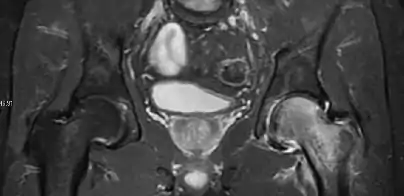

Magnetic resonance imaging

Many pathological conditions of the hip are detected early by MRI due to its high soft tissue resolution and sensitivity. Its accuracy in studying acute hip pain in children has proved to be superior to ultrasound and plan film radiography. However, MRI accessibility and the need of sedation relegate its use to selected cases in which diagnosis is not clear with less demanding techniques. These include differentiating transient synovitis from a septic arthritis or osteomyelitis, diagnosis of inflammatory joint disease or bone tumors, and early detection and follow-up of Perthes disease.[1]

In adults, MRI is currently playing a definite role in the assessment of osteoarthritis. Although traditionally belonging to the arena of radiographs, the role of MRI has been stressed after the term femoral acetabular impingement was coined in 2003. Growing interest has been focused in accurate diagnosis of the acetabular and femoral morphological abnormalities that may lead to early osteoarthritis.[1]

MR imaging is considered paramount to these objectives, mainly when surgery is considered, due to the ability of MRI to portray the whole section of the femoral neck surface, as well as to image the labrum and articular cartilage.[1]

Most of the angles and measurements described in the plain radiograph section can be accurately reproduced on MRI. In addition, the superiority of MRI resolution with intra-articular contrast allows detection of labral and chondral abnormalities that may influence the choice of medical, percutaneous, or surgical management (Figure 9).[1]